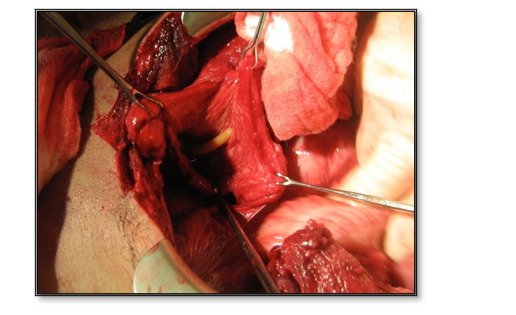

With the rise in dismounted complex battle injuries from explosive devices during combat operations in Iraq and Afghanistan and polytrauma involvement of the lower extremities, perineum, pelvis, and lower abdomen, greater attention has turned to the management of soft tissue injury to the external genitalia and urethra. Testicular injuries are easily missed due to small scrotal entry wounds in some cases and require a high index of suspicion when evaluating patients with significant blast injuries. If you are suspicious of penetrating trauma or believe it may be possible, a low threshold should be employed to explore the scrotum bilaterally. This holds true for blast injuries, as overpressure can cause testicular rupture in patients with no overt injury; a low threshold should be employed in these patients. (See Figure 8).

Figure 8. Top left: Testicular rupture seen in the setting of a blast injury. Top right: No overt testicular trauma was seen. The decision was made to explore. Bottom images: One of the testes was salvaged, where likely, both would be unsalvageable if not explored or treated early.  (Images courtesy of ZRM).